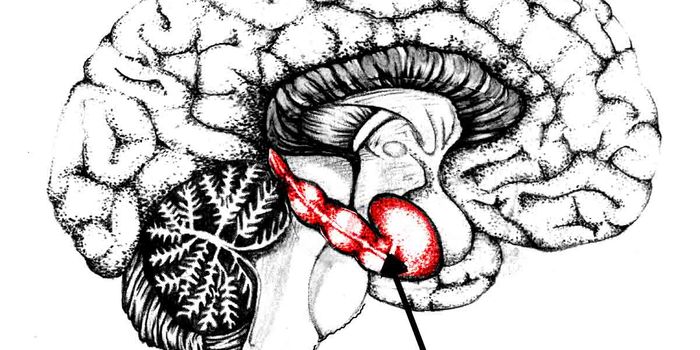

FEB 13, 2016NeuroscienceNew evidence shows mice have a brain structure that throttles rage. The structure is called the lateral septum. It&rsquo ...